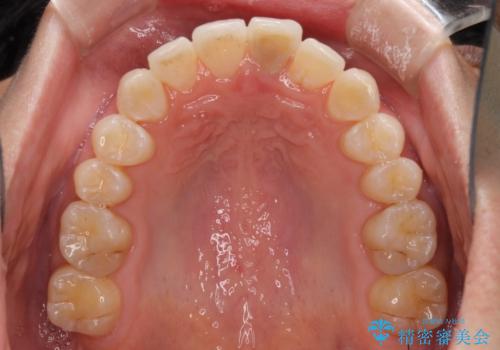

- 前歯のデコボコを治したいとのことで来院された患者様です。

上下顎ともに歯列全体の後方移動とIPR(歯と歯の間を削る)によってデコボコが解消するように設計し、インビザラインにより治療を行うこととしました。